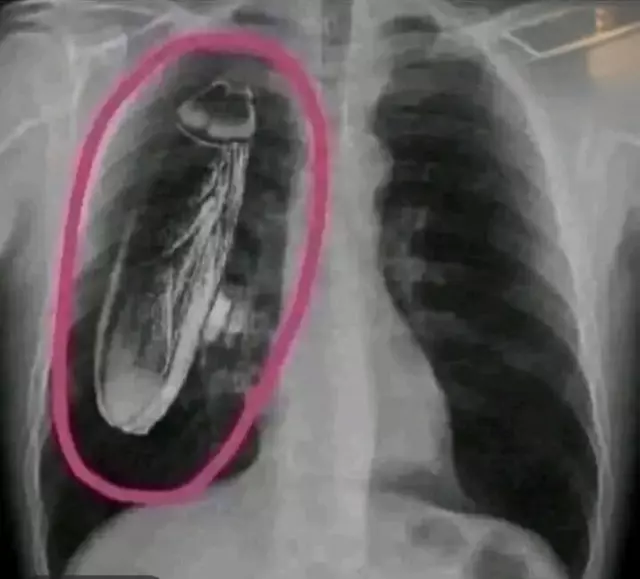

Röntgende Canlı Böcek Şaşkınlığı: Gerçek Hastanın Göğsünde Değil, Cihazda

Kenya'da bir devlet hastanesinde röntgeni çekilen hastanın göğsünde canlı hamam böceği olduğu iddia edildi. Singapur'da yapılan detaylı inceleme ise böceğin hastanın içinde değil, röntgen cihazında olduğunu ortaya koydu.

Kenya’nın bir devlet hastanesinde, göğüs röntgeni çektiren bir hastaya, görüntülerde canlı bir hamam böceği olduğu söylendi. İlk başta bu haber, tıbbi hatalar ve hijyen konularında büyük bir endişe yarattı.

Hastanın röntgeni, Kenya’da bulunan bir devlet hastanesinde çekildi. Görüntülerde, göğüs bölgesinde hareket eden bir nesne görülmüş ve bu nesne bir canlı böcek olarak yorumlanmıştı. Olay, sosyal medyada hızla yayılarak halk arasında büyük bir merak uyandırdı.

Olayın ardından Singapur’daki bir medikal uzman ekibi, aynı röntgen filmini detaylı bir incelemeye aldı. Uzmanlar, görüntüdeki canlı nesnenin röntgen cihazının içinde, cihazın bir parçası olarak sıkışıp kalmış bir hamam böceği olduğunu belirledi.

Bu bulgu, hastanın sağlığını etkileyen bir durum olmadığını ve olayın tamamen ekipman kaynaklı bir yanılgı olduğunu ortaya koydu. Uzmanlar, benzer durumların önlenmesi için röntgen cihazlarının periyodik bakımının önemine dikkat çekti.

Sonuç olarak, hastanın göğsünde bir canlı böcek olmadığı, sadece röntgen cihazının içinde bir böcek olduğu kanıtlanmıştır. Olay, tıbbi görüntüleme süreçlerinde dikkat ve ekipman kontrolünün ne kadar kritik olduğunu bir kez daha hatırlattı.